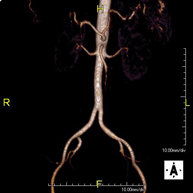

Prueba diagnóstica no invasiva que consiste en el estudio de la arteria aorta abdominal de las arterias ilíacas, obteniendo imágenes de alta definición anatómica mediante el empleo de un campo electromagnético y ondas de radio (con un emisor y un receptor). Es indispensable el uso de contraste paramagnético (Gadolinio). Sin embargo, no utiliza radiación ionizante. La calidad de las imágenes permite realizar reconstrucciones en 2D y 3D. Esta prueba está especialmente indicada como estudio pre-quirúrgico (mapa vascular) antes de intervenciones percutáneas o quirúrgicas de aorta abdominal y arterias ilíacas, estudio complementario en pacientes con isquemia de miembros inferiores, etc. - Angio RM Arterial extremidades inferiores

Prueba diagnóstica no invasiva que consiste en el estudio vascular del sector aorto-ilíaco y de los vasos arteriales de ambas extremidades inferiores, obteniendo imágenes de alta definición anatómica mediante el empleo de un campo electromagnético y ondas de radio (con un emisor y un receptor). Es indispensable el uso de contraste paramagnético (Gadolinio). Sin embargo, no utiliza radiación ionizante. La calidad de las imágenes permite realizar reconstrucciones en 2D y 3D. Está especialmente indicado en aquellos pacientes en los que hay sospecha de enfermedad vascular de ambas extremidades, en pacientes con enfermedad vascular de ambas extremidades como el mapa vascular antes del tratamiento (percutáneo o quirúrgico), como el mapa vascular pre-quirúrgico en pacientes con lesiones óseas o musculares que requieran cirugía, etc. - Angio-RM Arterias renales